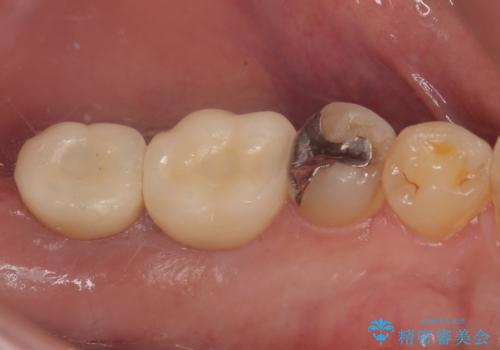

- 以前、咬合力の強さで歯の神経が失活してしまい、当院にて根管治療を行った患者様ですが、今度は咬合力の影響で歯根が破折してしまった患者様です。

歯根が破折してしまった歯は抜歯が必要となり、特に咬合力が強い方ですと、インプラント治療による治療がお勧めとなります。